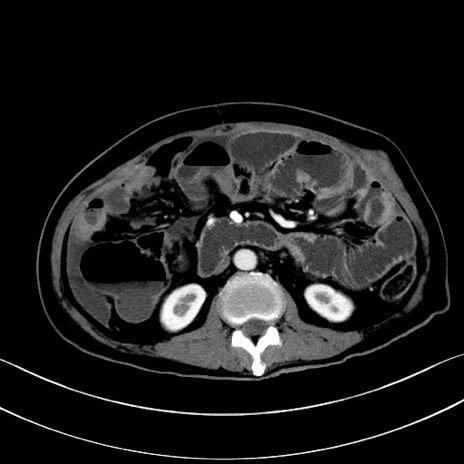

症例28(横断像)

【症例】60歳代男性

【主訴】嘔吐

【現病歴】胃癌にて胃全摘後。食思不振が悪化し、夜中に嘔吐することがある。

【既往歴】胃癌、胃全摘、脾摘、胆摘後

【データ】WBC 5900、CRP 10.56